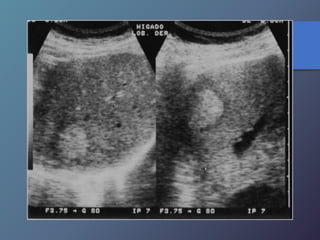

Metástasis

• Su incidencia depende del tipo de tumor.

• Localizaciones mas frecuentes del TU primario:

vesícula biliar, colon, estomago, páncreas, mama y

pulmón.

• Pueden presentar una sola lesión hepática, aunque

suelen tener múltiples masas focales.

Mt Hiperecoicas

• Ecográficamente se presentan las lesiones

de tamaño variable con presencia de un

halo hipoecoico.

• Diferenciar lesiones malignas de benignas

por presencia de halo hipoecoico.

• Se describen como lesiones ecógenas,

hipoecoicas, en diana, calcificadas,

quísticas y difusas.